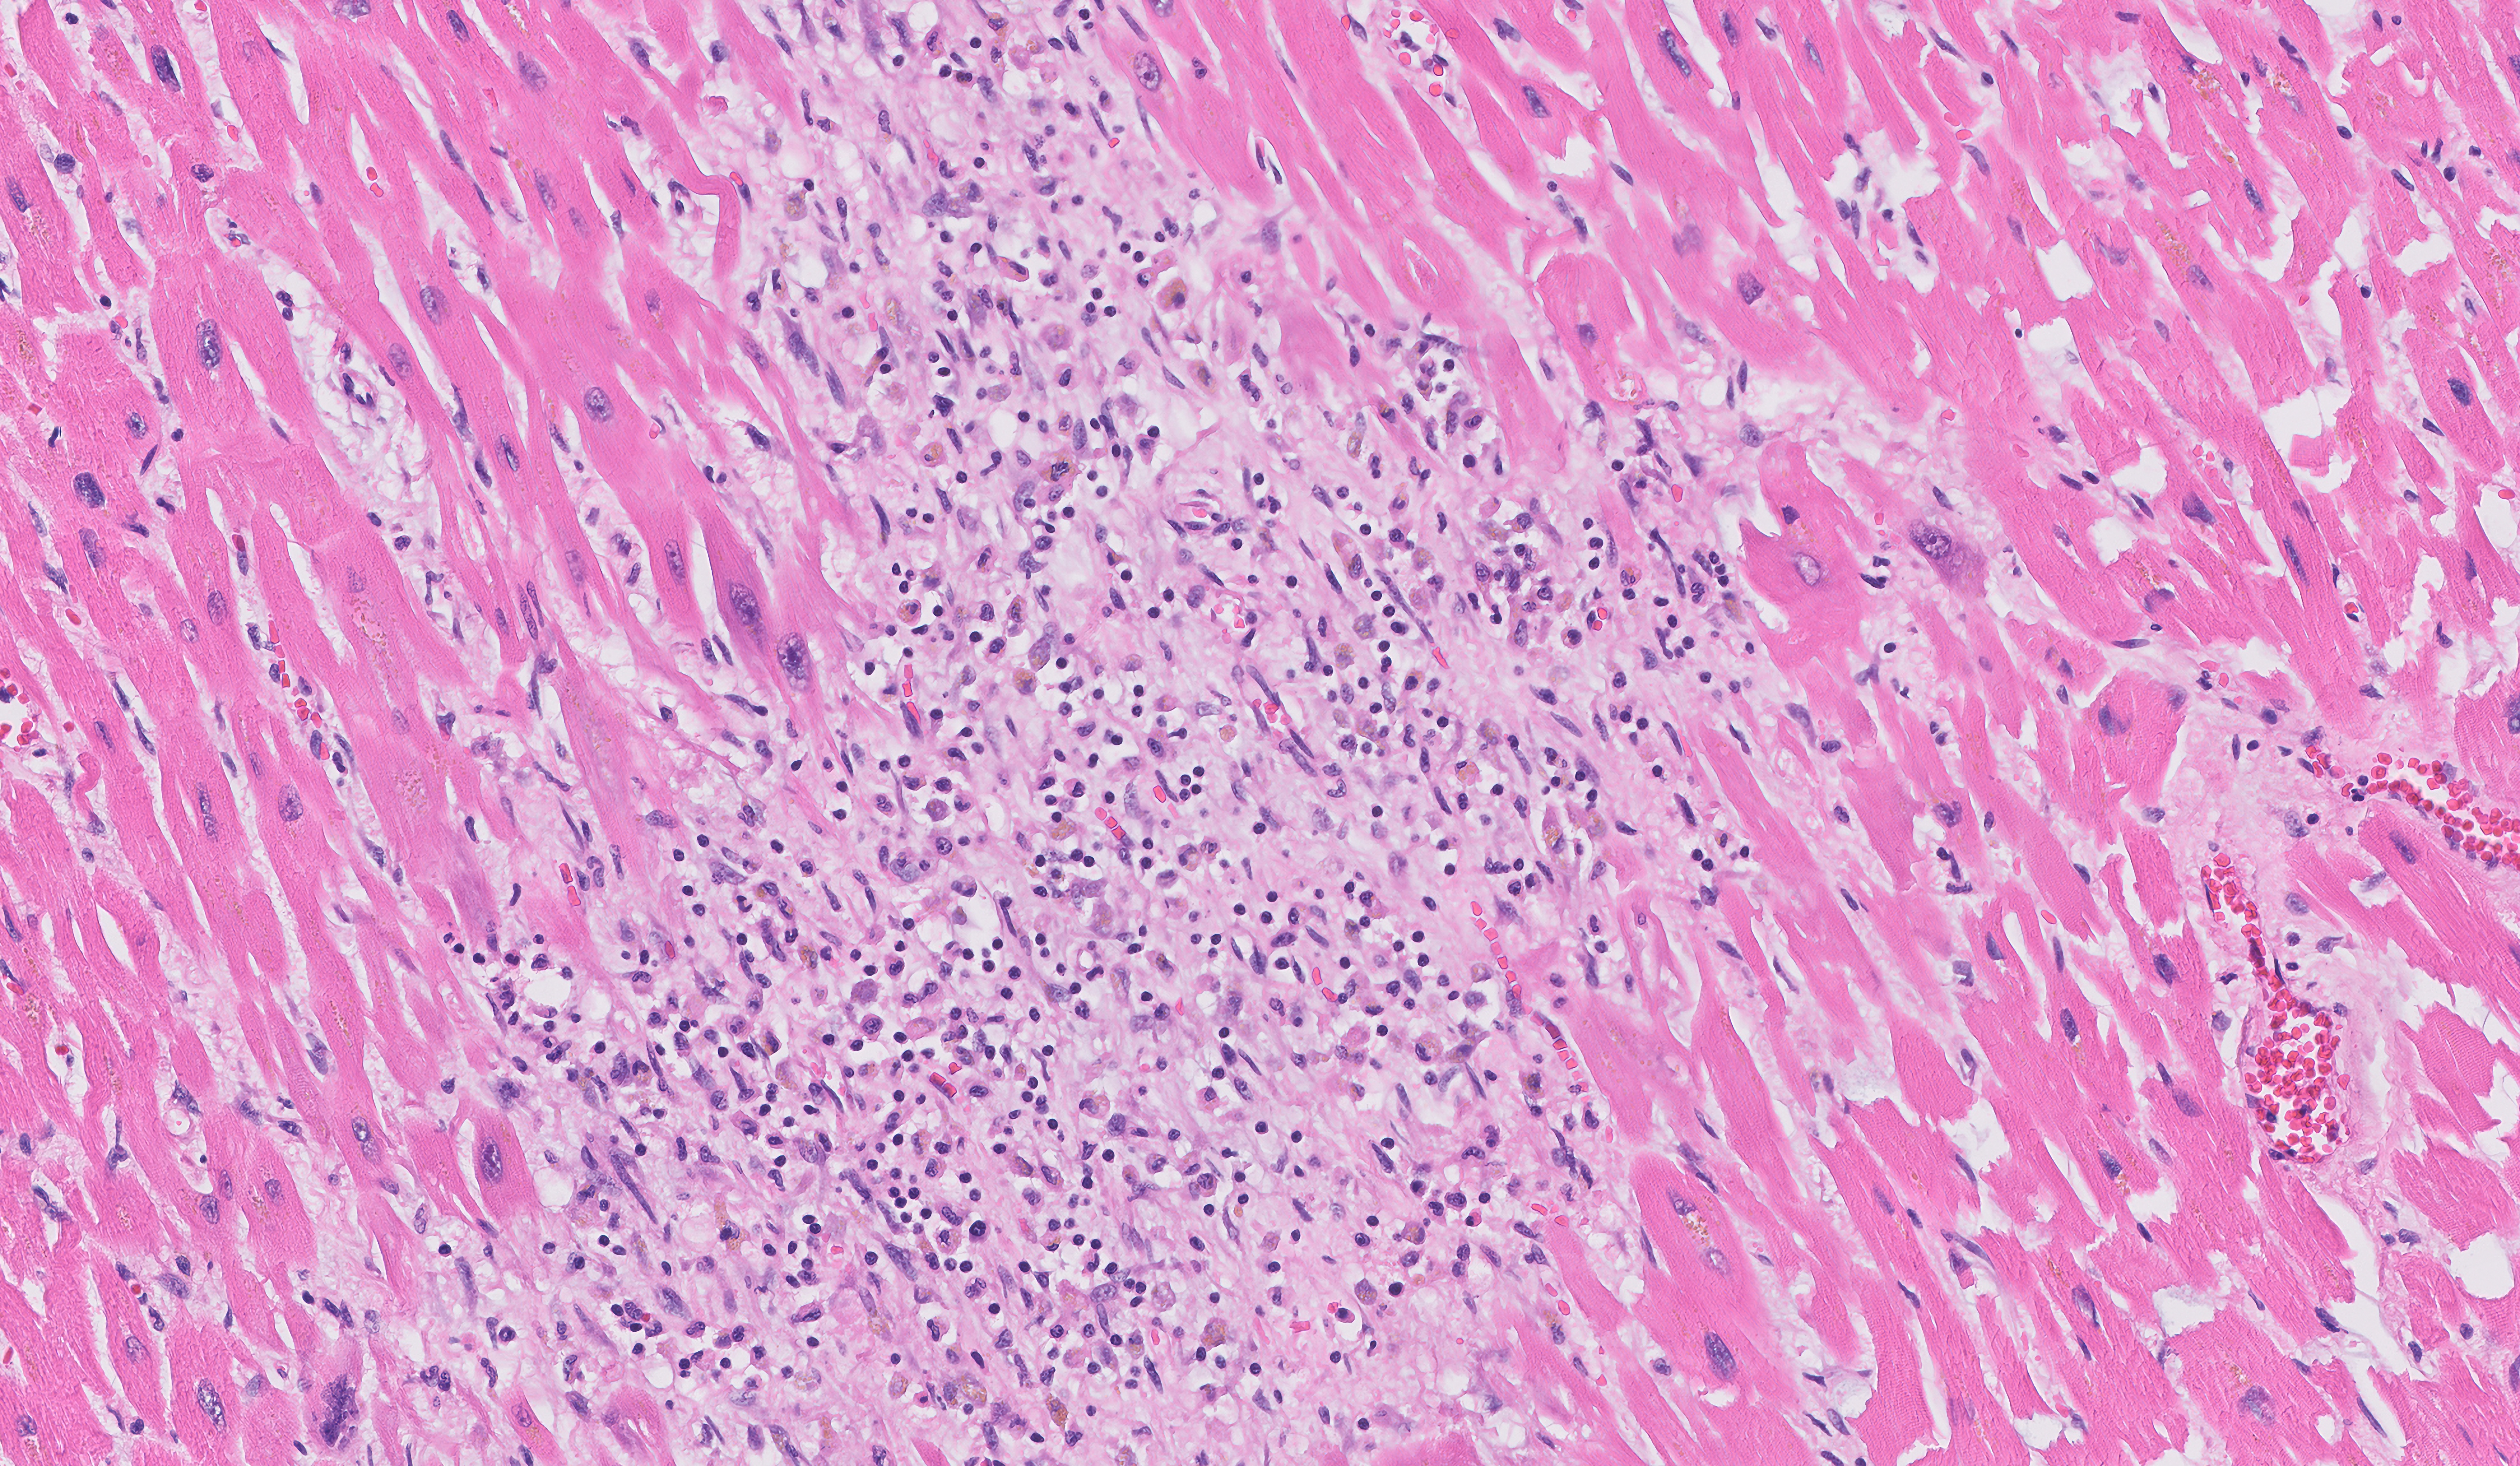

| 3-7 days | Myocyte loss, karyorrhexis of neutrophils (“nuclear dust”), early phagocytosis by macrophages at infarct border, early granulation tissue and capillary proliferation at the edges |

| 7-10 days | Well-developed phagocytosis with distended macrophages |

| 10-14 days | Well-established granulation tissue with new blood vessels and fibroblast infiltration, hemosiderin-laden macrophages, some plasma cells/eos, neutrophils are gone |